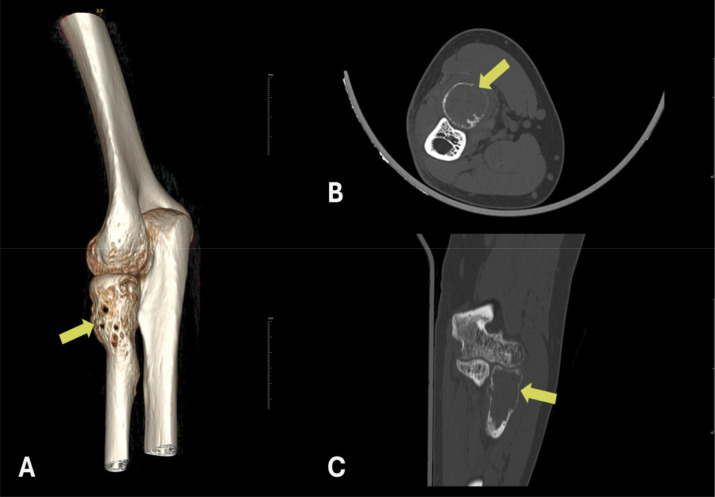

30岁男性左肘疼痛肿胀。多模态放射学评估显示一个扩张性溶解性骨病变,伴有液体-液体水平和周围软组织水肿,局限于桡骨头。组织学检查证实了动脉瘤性骨囊肿(SVABC)的实变,这是一种解剖学上罕见的病变。病变经过刮除处理,导致完全的临床解决。教学要点:结合影像学和组织学发现,准确诊断和有效治疗SVABC,特别是当发生在非典型部位时,它们可能模仿更侵袭性的肿瘤。

A 30-year-old male presented with pain and swelling in the left elbow. Multimodal radiologic evaluation revealed an expansile, lytic bone lesion with fluid-fluid levels and surrounding soft tissue edema, localized in the radial head. Histological examination confirmed the diagnosis of a solid variant of aneurysmal bone cyst (SVABC), an anatomically rare site for such lesions. The lesion was managed with curettage, leading to complete clinical resolution. Teaching point: integrating radiologic and histologic findings to an accurate diagnosis and effective management of SVABC, especially when occurring in atypical locations where they may mimic more aggressive neoplasms.